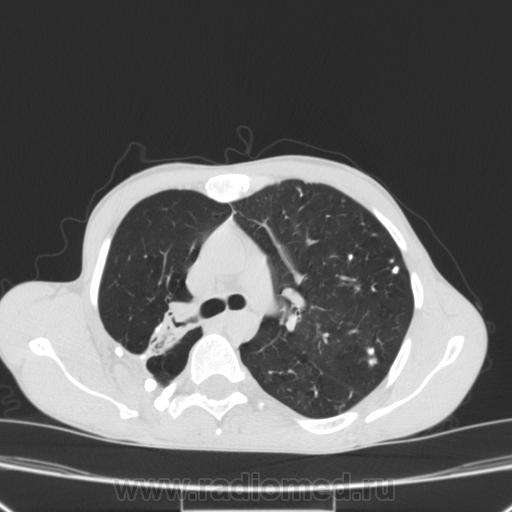

Состояние после торакопластики.

Молодой человек 30 лет, в 04 году выявлен фиброзно-кавернозный ТБ, в течение 12 месяцев лечился в стационаре, прооперирован-5реберная торакопластика справа, через 3 года переведен в 3ГДУ, в 10году снят с ДУ по излечению. Пришел провериться по ухудшению состояния. На КТ легких данных за рецидив ТБ, вроде нет. С " торакопластикой" был единственным пациентом на учете.

Состояние после правосторонней 5-реберной торакопластики по поводу ФКТ.Грубые остаточные изменения:поликистоз,буллезно-дистрофические изменения,плевропневмоцирроз правого легкого..Нет ли  мелкоочаговой диссеминации в обоих легких?Нужен Rархив.(ПТД).

Нет, это кальцинаты и более плотные уже. Архив только пленочный, 8 лет назад "цифры" не было. Можно и пленку перефотать...

Редко встречалось, а на КТ вижу впервые, спасибо за случай! На показанных изображениях отсевов не увидела.